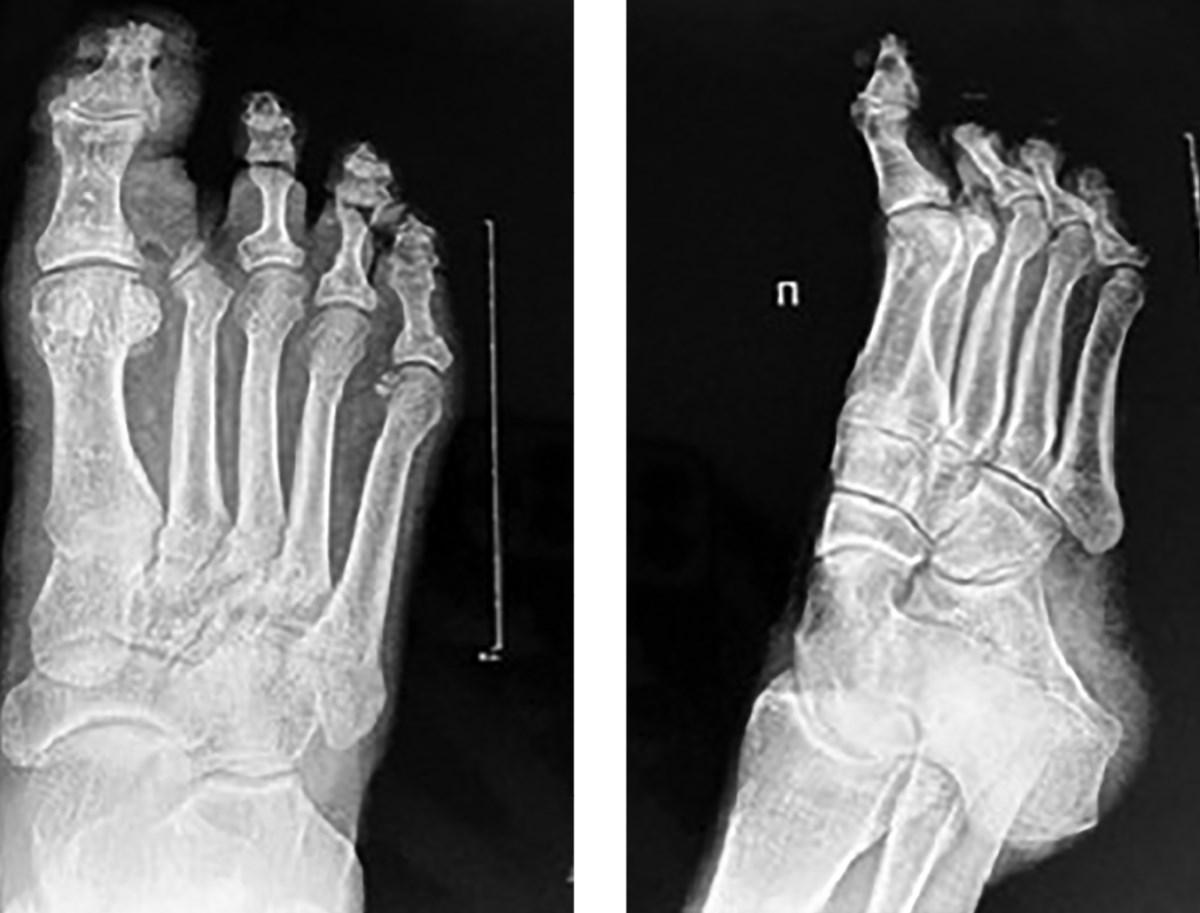

На снимках рентгенографии правой стопы в двух проекциях выявлены признаки дегенеративно-дистрофических изменений и остеоартроза (рис. 2). Уменьшена ширина суставных щелей первого плюснефалангового сустава и межфалангового сустава первого пальца, наблюдается субхондральный склероз и заострение суставных поверхностей. Эти изменения могут быть обусловлены нарушениями кровообращения и хроническим воспалением, характерными для диабетической нейропатии и ангиопатии, и они усугубляют состояние суставов и костной ткани при СДС.

Рисунок 2. Рентгенограмма правой стопы в двух проекциях. Уменьшена ширина суставных щелей первого плюснефалангового сустава и межфалангового сустава первого пальца, наблюдается субхондральный склероз и заострение суставных поверхностей.